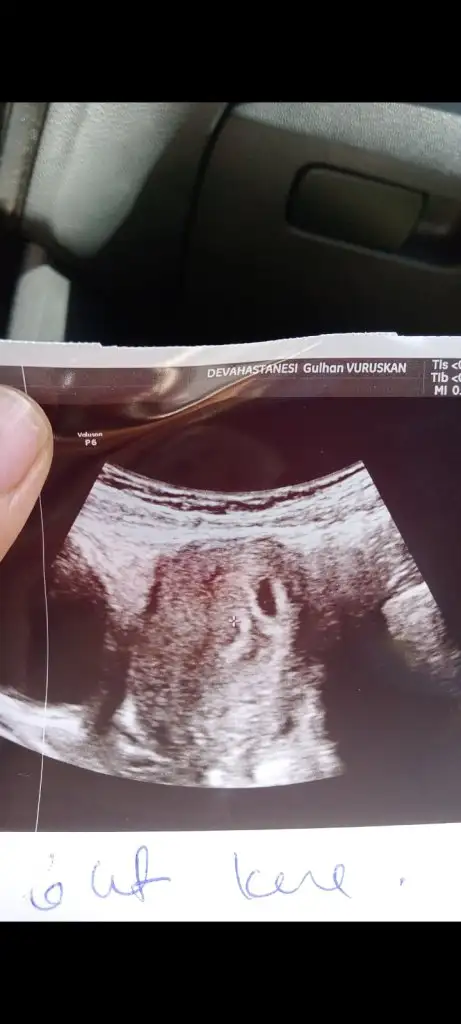

Merhaba, ben bebeğimi kaybettim.. 8 haftalıkken kalbi durdu. 9+5’te doktor muayenesine gittiğimde öğrendim. Öğrendiğimin ertesi günü de kürtaj oldum. Cinsiyetini hep çok merak ettim. Sürekli Çin, Rus, Maya takvimi vs bakıp duruyordum. En azından doğruluğu kesin olmasa bile, teoride bile olsa benim meleğim için de tahminde bulunabilir misiniz? Bu görüntü karından ultrason ve 6+4’teyken çekilmişti. Rabbim bebek bekleyen herkesin sağlıkla kucağına almasını nasip etsin.

Eklentiler

• IMG_6244.webp

IMG_6244.webp

7,1 KB · Görüntüleme: 199